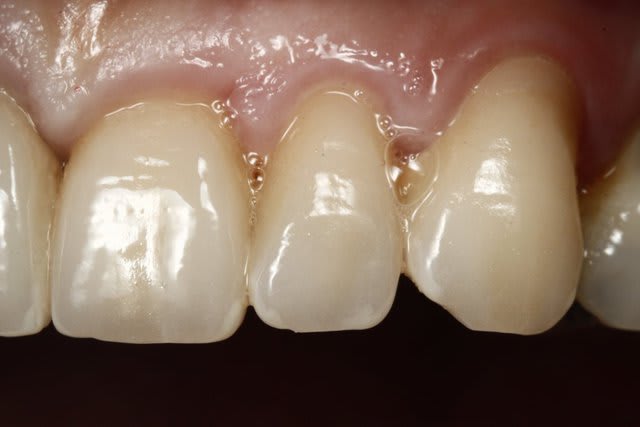

Un cas avec des collets... traité avec Couronne emax et Facettes....

Les collets sont pas si mal placés. Il faut faire un wax up pour voir la forme finale des dents. Bien aussi regarder où se situe le bord libre par rapport aux lèvres. si il est au bon endroit on peut en venant sur les racines redonner la forme naturelle aux dents.

En cervicale il n'y aura quasiment pas de préparation.

C'est une indication de facette.

Garder à l'esprit que sur cette dentine cervicale tu colleras moins bien.